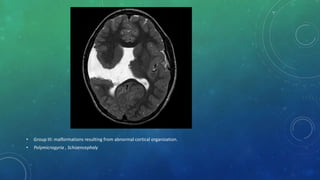

• Group III: malformations resulting from abnormal cortical organization.

• Polymicrogyria , Schizencephaly